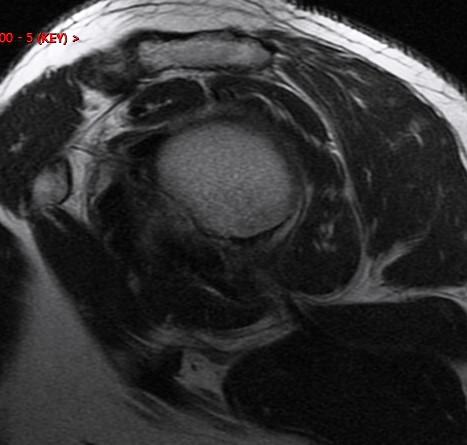

Discussion

Anterior humeral impaction fracture of the lesser tuberosity and posterior labrum tear. The periosteum of the scapula looks intact so maybe should be called a reverse Perthes lesion. Injury occurs when a posterior force occurs to the shoulder (front to back) when the shoulder is internally rotated and flexed. Classic examples are tonic clonic seizure with the patient falling with decorticate rigidity forward and hitting the ground. Also American football lineman in 3 point stance (internal rotation and some flexion) hit by another player moving towards him when the ball is hiked. Typically the other player is as large as a refrigerator.

Diagnosis

Reverse bankart and hill sachs lesions